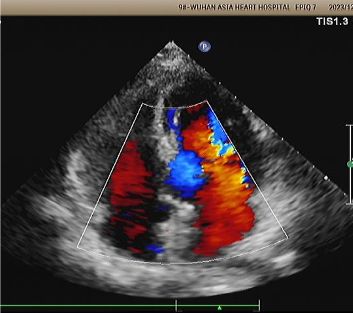

Eco de 1 año:

No visible disc structures – replaced by 8mm tissue thickening at the septal implant site.

Zero residual shunt (rest or post-Valsalva).

Se ha confirmado la absorción completa del dispositivo.